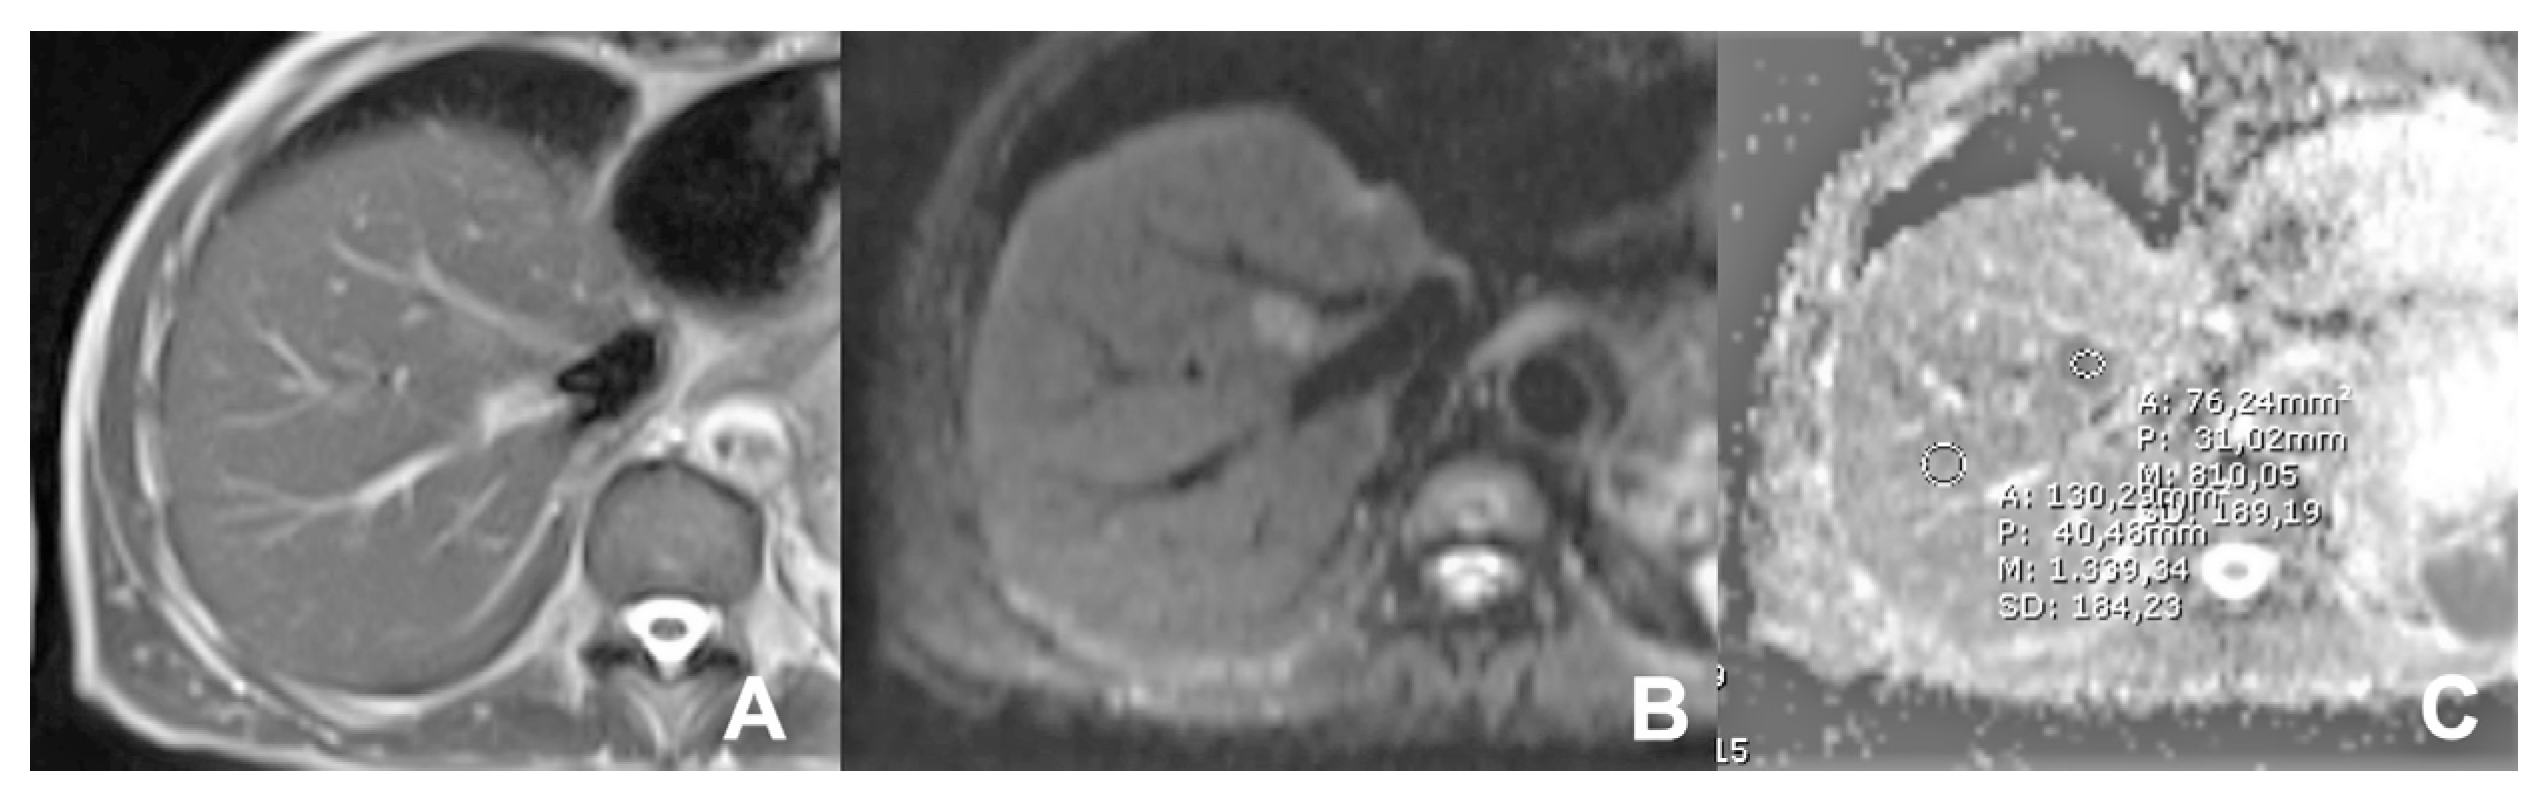

| DWI b 0–50–400–800 | AXIAL | -- | -- | Restricted diffusion most likely malignant | |

| GRE T1 IN/OUT | AXIAL | -- | -- | Steatosis | |

| DWI b 0–50–400–800 | AXIAL | -- | -- | High signal in b 800 suspicious for HCC | |

| DWI b 0–50–400–800 | AXIAL | -- | -- | DWI b50 increases the sensitivity of mets detection | |

| DWI b 0–50–400–800 | AXIAL | -- | -- | Abscess in ADC map is hypointense | |

| Iron/fat quantification | HASTE T2 | AXIAL | -- | -- | Anatomy and liquids analysis |

| Indications: MRI is the technique of choice to quantify the amount of fat or iron overload. | HASTE T2 | CORONAL | -- | -- | Anatomy and liquids analysis |

| GRE Multi echo | AXIAL | -- | -- | For the quantification of fat and iron content | |